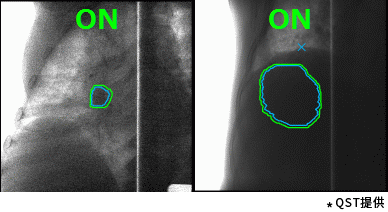

東芝的重離子癌癥放射治療系統具有高速3D掃描,患者自動(dòng)定位,小型化重離子旋轉機架(搭載東芝自研超導磁鐵實(shí)現重量和體積的大幅縮?。┑炔町惢夹g(shù)。實(shí)時(shí)成像的呼吸門(mén)控是照射技術(shù)與重復掃描技術(shù)的結合,能夠對伴隨呼吸運動(dòng)的腫瘤進(jìn)行快速、準確的照射,且保證劑量分布均一性。特別是,東芝憑借自身先進(jìn)的超導技術(shù)的加持,使旋轉機架得以逐漸小型化。這一成果直接推動(dòng)了重離子旋轉機架的商業(yè)化普及。應用旋轉機架治療,可從360度任意角度進(jìn)行照射,避開(kāi)正常組織和危及器官。治療過(guò)程中一次定位,避免了移動(dòng)患者造成的內部臟器位移,實(shí)現精準治療,同時(shí)提高治療效率,增加治療人數,在同類(lèi)型產(chǎn)品中獨具技術(shù)優(yōu)勢。

高速掃描+呼吸門(mén)控照射(動(dòng)圖) |